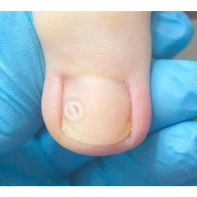

В связи с постоянной травматизацией ногтевых пластин во время хирургического удаления, возможно формирование деформированных ногтей. Ногтевые пластины формируются суженными за счет глубоко посаженных краев в боковые пазухи кожных валиков. Для этого существуют коррекционные системы (скобы, пластины), которые принудительно расширят ногтевые пластины и зададут правильный вектор для роста ногтя.

Онихокриптоз, или вросший ноготь, – одно из самых распространенных заболеваний ногтей, чаще всего затрагивающее большие пальцы ног и вызывающее сильную боль, отек и воспаление. Если степень врастания небольшая, используются консервативные методы коррекции, не требующие операционного вмешательства. Лечение проводится специалистом-подологом при помощи различных пластинчатых и проволочных конструкций и протекторов, которые постепенно разгибают деформированный ноготь и придают ему правильную форму.

Вросший ноготь (или онихокриптоз) – это болезнь, при которой ногтевая пластинка врастает в боковую часть кожного валика. Чаще всего это явление возникает на большом пальце стопы. В таком случае возникает боль, отек валика, гиперемия и не редко серозно-гнойное отделяемое. В таком случае, чаще всего, проводится краевая резекция врастающей части ногтевой пластины.

В вопросе, скорее, речь идет о синдроме оплывшего дистального валика, что является проявлением ониходистрофии, и может появляется после отслоения ногтевой пластины на фоне длительного давления или травмы, а также после длительного отсутствия ногтевой пластины после ее удаления. В таком случае ногтевое ложе остается частично не прикрытым, и кожа дистальной части околоногтевого валика, накрывает оголенное ложе. Тем самым ногтевая пластина, отрастая, встречает «преграду» в виде валика и травмирует его.

В данном случае необходима чистка ногтевой пластины и установка коррекционных систем. Иногда подолог может установить тампонады или протезирующий материал для поднятия ногтевой пластины над ложем. Все зависит от клинической картины и выраженности закрытия ложе дистальным валиком. Данные манипуляции проводятся 1 раз в 2-4 недели, сроки так же зависит он выраженности клинической картины.